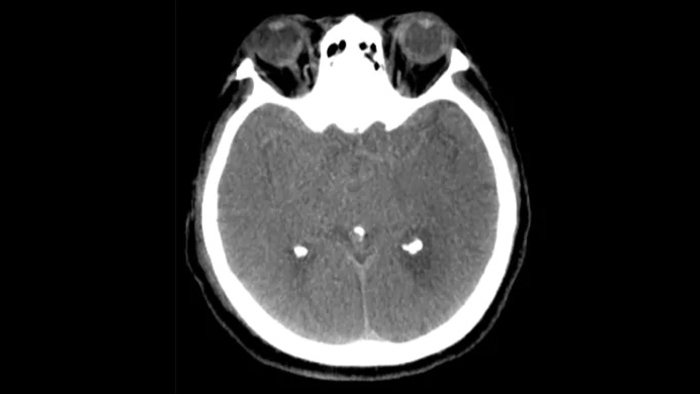

Control periprocedimiento de hemorragias

SmartCT soft tissue

Use las imágenes de SmartCT Soft Tissue (similar a una TC) de la suite Neurovascular para comprobar el éxito del tratamiento e identificar hemorragias.